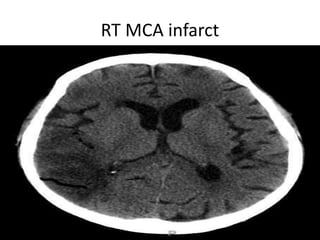

RT MCA infarct

Vascular Insults • SubarachniodHemorrhage. • Lobar and basal ganglia bleeds. • Ischemic strokes. • Venous infarcts. • Disections